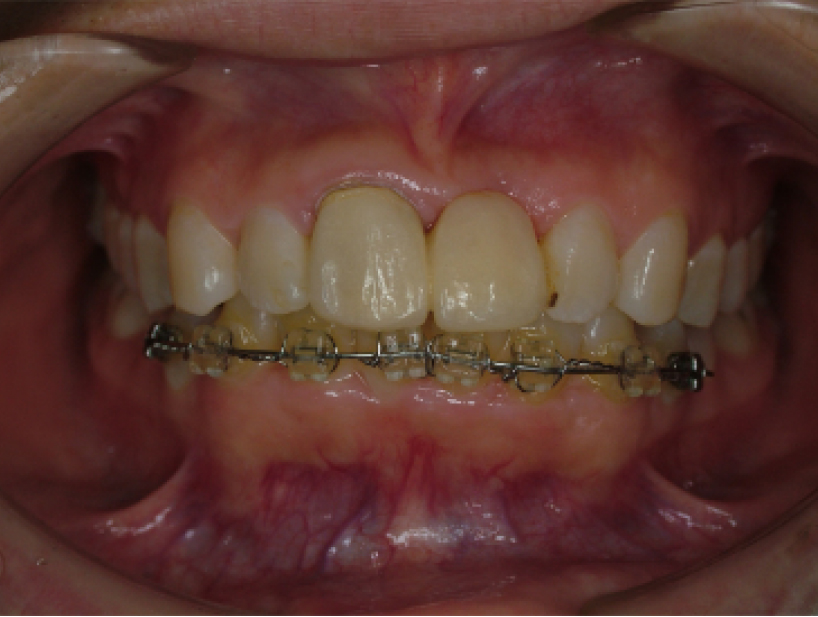

治療前治療後

| 治療内容 | 前歯インプラント治療/下前歯矯正治療 |

|---|---|

| 患者様の年齢 | 19歳 |

| 患者様の性別 | 女性 |

| 治療期間 | 1年 |

| 治療回数 | 矯正治療合わせて45回程度 |

| 治療費用 | インプラント治療50万円/矯正15万円 |